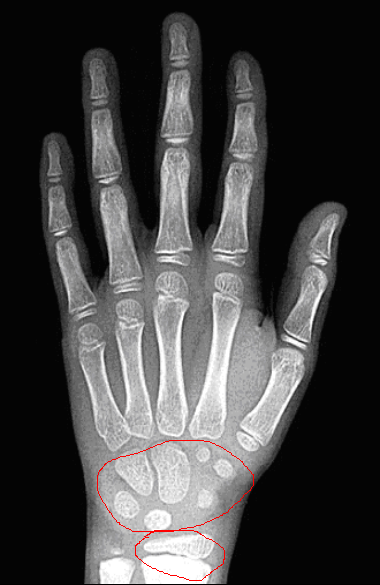

那我们怎么知道骨骺是否闭合了呢?可以通过骨龄来判断,通常来讲就是骨头的年龄,但是骨龄不一定等于一个时期的年龄。骨龄可以通过拍摄手掌骨的X片,一般拍的是左手,可以了解腕骨和掌骨的发育情况。

男孩6岁

男孩14岁

这是一个骨龄的片子,孩子身高不能够掉以轻心。首先,骨龄它不等于实际年龄,现在高也不意味着成年后一定高。目前男孩的骨龄16岁,女孩的骨龄14岁半基本上骨骺就接近了闭合。男孩骨龄14岁半和女孩骨龄12岁半身高会出现减速,一般来说,身高的年增长会小于2个厘米。身高增长有两个高峰,第一个高峰是0到2岁,出生的时候普遍的均身高是50厘米,第一岁的时候一般是75到76厘米,所以第一年生长大概是25到26个厘米左右,而两岁时可以到85到86厘米。从出生到两岁的整个过程,身高的一个增长速度是35到36个厘米。三岁到青春期间,这是一个生长的稳定期,大概是5到7个厘米每年。第二个生长高峰是在青春期,是性激素的作用开始的标志,如女童一般是乳房出现发育,多在9到14岁的时候,而男童一般是出现睾丸的增大,大部分出现在11到13岁。在这个标志开始以后一到两年会达到身高增长的峰值。整个青春期的生长,男童增长大概是25到30厘米,女童大概是25厘米,大概相当于0到1岁时的增长幅度。